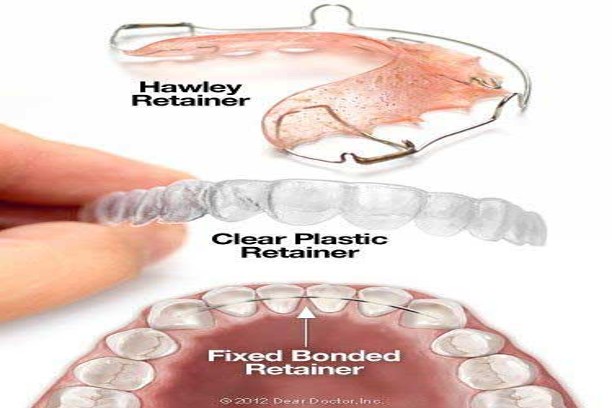

Retainers

Custom-made appliances to maintain tooth position after orthodontic treatment.